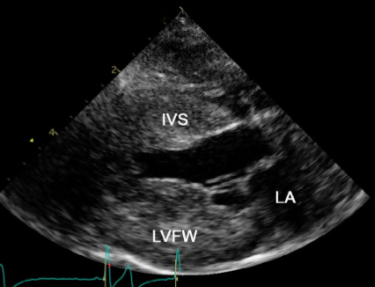

그러나 B mode상에서 확실한 심근의 비후 양상이 보이기 때문에 이보다 더 강력한 진단수단은 없다.